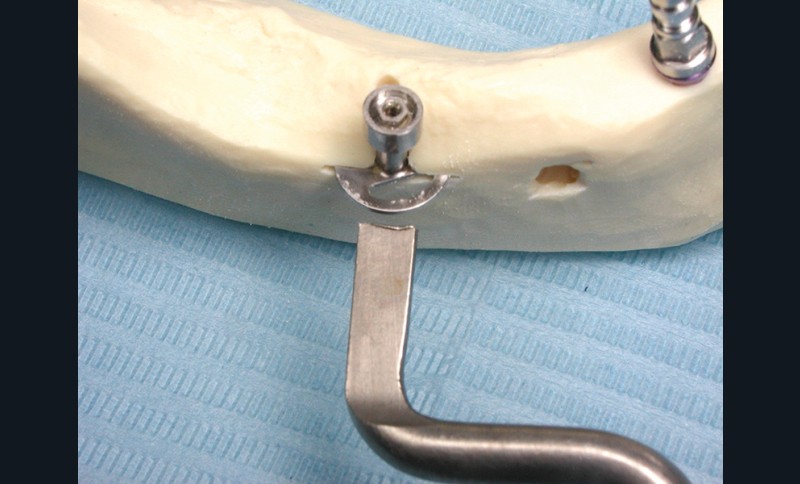

L’implantologie basale initiée par Jean-Marc Juillet [2] en 1972, et reprise en 1978 par Gérard Scortecci [3, 12, 13], est caractérisée par la pose d’implants disques spécialement conçus. Présentés officiellement pour la première fois à Munich en 1984, ces implants sont impactés latéralement à la suite d’une ostéotomie réalisée au niveau des bases osseuses dans les trois sens de l’espace à l’aide d’un cutter monté sur turbine sous spray (fig. 1). Ces Diskimplants en titane peuvent comporter d’un à trois disques de différents diamètres (circulaires ou asymétriques) et se caractérisent par un pilier intégré présentant un hexagone externe protégé par un carénage cylindrique conique [4, 7, 8].